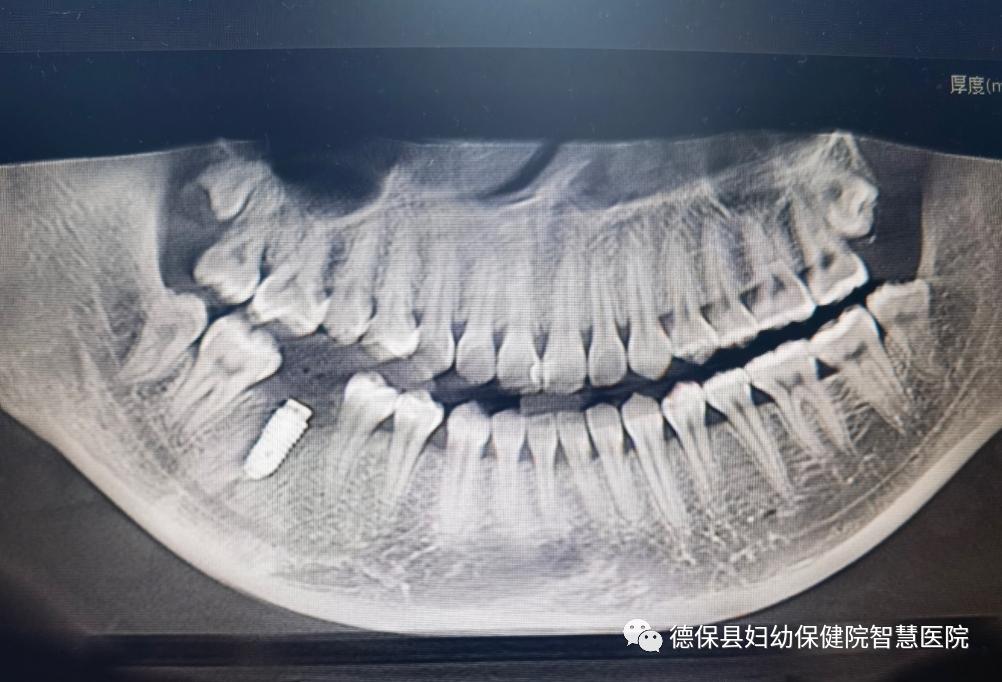

(术前全景照)

据悉,22岁的患者李女士,因右下后牙缺失4个月,慕名来我院口腔科门诊就诊,要求修复该牙,经门诊专科检查及相关影像学检查诊断为“右下第一磨牙缺失、牙槽骨愈合不良”。该缺失牙具有下颌骨较丰满、牙槽骨愈合不良、颊侧骨板缺如等特点,考虑到患者较年轻,应用活动义齿修复异物感强,应用固定义齿修复会损伤邻牙等因素,经张辉副主任医师会诊后决定,为该患者行右下第一磨牙种植修复术+同期颊侧骨壁GBR植骨术。